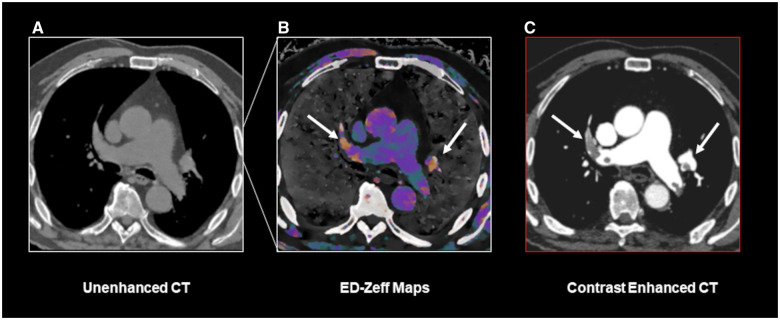

目的:本研究旨在评估利用电子密度(ED)图结合未增强双层双能CT (dl-DECT)扫描胸部获得的z有效(Zeff)图像检测肺栓塞(PE)的可行性。材料与方法:回顾性分析临床怀疑PE或急性主动脉综合征的连续行胸部CT (CECT)增强扫描患者。这些扫描在2021年10月至2023年11月期间在一台dl-DECT扫描仪上进行。为了区分栓子和循环血液,将ED数据集叠加在从未增强阶段获得的Zeff图像上生成彩色编码图。两名具有不同专业水平的放射科医生独立评估了生成的ED-Zeff图中PE的存在,对作为参考标准的CECT结果不知情。对每个阅读器的ED-Zeff图的诊断准确性进行评估。结果:最终研究队列包括150例患者,其中男性92例(平均年龄68±10岁,范围47-93岁),女性58例(平均年龄66±15岁,范围38-89岁)。ED-Zeff图谱表现出较高的诊断性能,准确度、敏感性和特异性分别为86.67% (113/150,95% CI, 80.16%-91.66%)、85% (17/20,95% CI, 79.89%-92.19%)和86.92% (113/130,95% CI, 79.89%-92.19%)。Ed-Zeff图谱能够在85%的阳性病例中识别出PE。Cohen’s kappa系数表明观察者内部和观察者之间的一致性很好(κ≥0.9)。结论:ED图结合未增强dl-DECT扫描的Zeff图像是一种检测PE的可行工具,可能在评估有碘造影剂禁忌症的患者时有用。

Materials and methods: A retrospective analysis was conducted on consecutive patients who underwent for contrast-enhanced chest CT (CECT) clinically suspected of PE or acute aortic syndrome. These scans were performed on a single dl-DECT scanner between October 2021 and November 2023. To distinguish emboli from circulating blood, color-coded maps were generated from the ED dataset superimposed on Zeff images, which were acquired from the unenhanced phase. Two radiologists with different levels of expertise independently assessed the presence of PE in the generated ED-Zeff maps, blinded to CECT results, which served as the reference standard. Diagnostic accuracy of ED-Zeff maps was assessed for each reader.